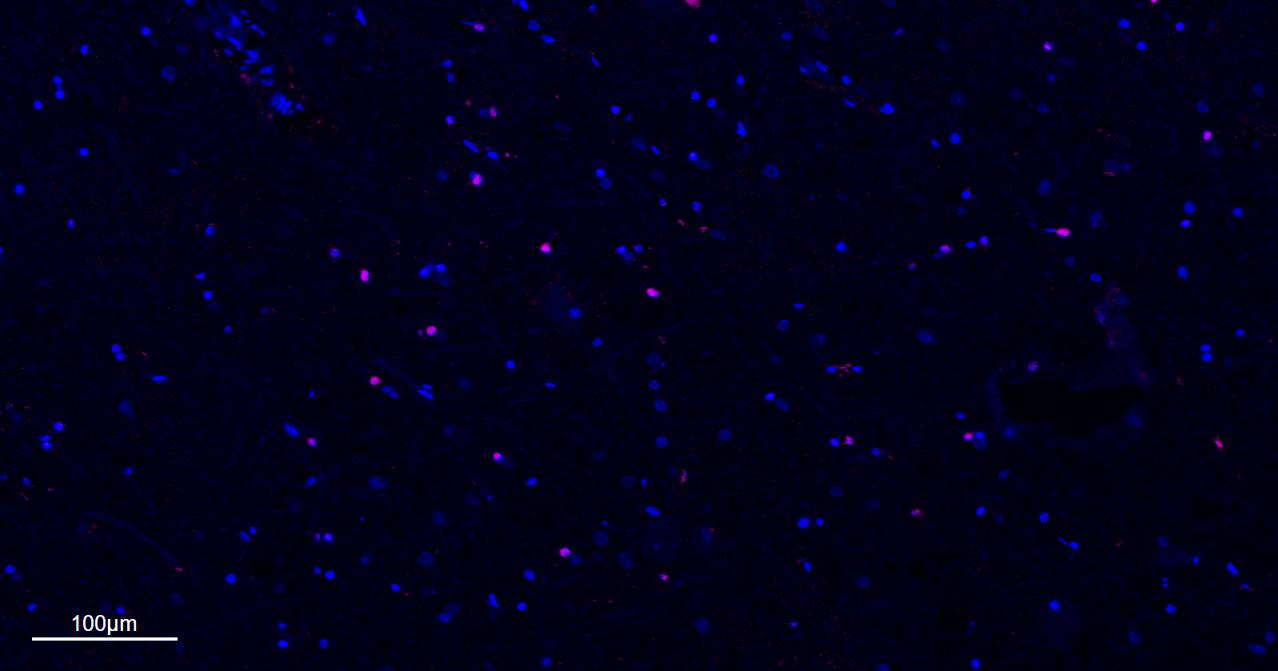

Paraformaldehyde-fixed, paraffin embedded Rat Cerebrum; Antigen retrieval by boiling in sodium citrate buffer (pH6.0) for 15 min. The first round ,antibody incubation with MBP Monoclonal Antibody, Unconjugated (bsm-33932M) at 1:200 overnight at 4°C. Followed by conjugated Goat Anti-Mouse IgG antibody (green, bs-0296G-BF488). The second round , antibody incubation with Olig2 Monoclonal Antibody, Unconjugated (bsm-61115R) at 1:200 overnight at 4°C. Followed by conjugated Goat Anti-Rabbit IgG antibody (red, bs-0295G-BF594). DAPI (blue, C02-04002) was used to stain the cell nuclei.

Paraformaldehyde-fixed, paraffin embedded Mouse Cerebrum; Antigen retrieval by boiling in sodium citrate buffer (pH6.0) for 15 min. The first round ,antibody incubation with MBP Monoclonal Antibody, Unconjugated (bsm-33932M) at 1:200 overnight at 4°C. Followed by conjugated Goat Anti-Mouse IgG antibody (green, bs-0296G-BF488). The second round , antibody incubation with Olig2 Monoclonal Antibody, Unconjugated (bsm-61115R) at 1:200 overnight at 4°C. Followed by conjugated Goat Anti-Rabbit IgG antibody (red, bs-0295G-BF594). DAPI (blue, C02-04002) was used to stain the cell nuclei.